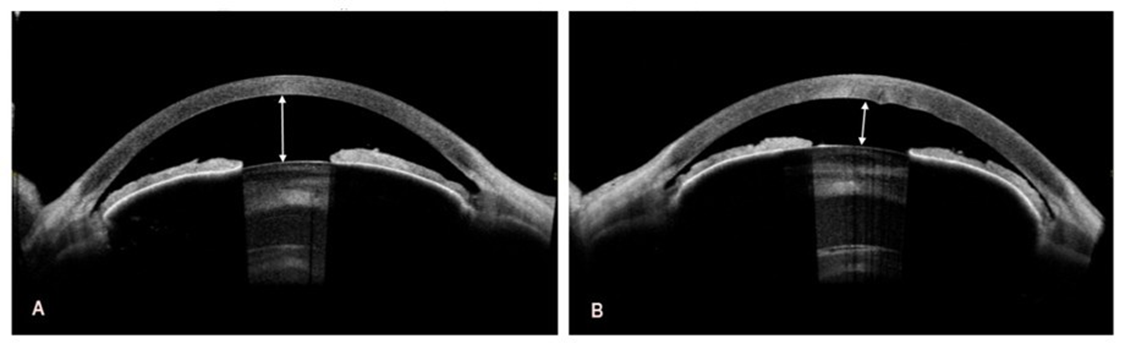

Distance visual acuity, assessed using Snellen charts, was 0.15 in

the right eye and counting fingers in the left eye. Optical correction did not improve visual acuity. Since the autorefraction test could not be performed, spectacle correction was empirical. Intraocular pressure, measured using a non-contact iCare tonometer (Icare Finland Oy, Vantaa, Finland), was 22 mmHg in the right eye and 23 mmHg in the left eye. Due to corneal edema, particularly in the left eye, these values may have been underestimated; therefore, digital palpation confirmed mildly elevated ocular tension bilaterally. Endothelial cell density in the right eye was 1469 cells/mm²; measurement could not be performed in the left eye because of advanced bullous keratopathy. Slit-lamp examination revealed bilateral corneal edema, more pronounced in the left eye, shallow anterior chambers, and brunescent, subluxated cataracts. Fundus visualization in the right eye was limited, with only the outlines of the optic disc and retinal vessels visible, and a preserved red fundus reflex visible. No fundus view was obtainable in the left eye. Anterior segment imaging using spectral-domain optical coherence tomography (SD-OCT; REVO 80, Optopol Technology Sp. z o.o., Zawiercie, Poland) showed a hyperreflective endothelium with normal Central Corneal Thickness (CCT) in the right eye (Figure 1A) and corneal edema with increased corneal thickness and Descemet membrane folds in the left eye (Figure 1B).

Figure 1: Preoperative spectral-domain optical coherence tomography of the right and left eye. A. In the right eye, the central corneal thickness is 547 µm. B. In the left eye, the central corneal thickness is increased by 729 µm with Descemet membrane folds. The corneal epithelial thickness map shows focal epithelial thickening consistent with edema with bullous keratopathy.

The patient attended regular follow-up appointments throughout the treatment course. Postoperative management for both eyes included dorzolamide (Rozalin, Adamed Pharma S.A. Pieńków, Poland) twice daily, 0.1% dexamethasone (Polpharma S.A., Starogard Gdański, Poland) five times daily, and a fluoroquinolone antibiotic (Oftaquix; Santen Oy, Tampere, Finland) five times daily. A transient increase in corneal thickness was observed one month after cataract surgeries in both eyes. CCT was 637 µm in the right eye and 713 µm in the left eye. A significant improvement in visual acuity in both eyes was observed four months after surgery, allowing reliable autorefraction measurements. In the right eye, Uncorrected Visual Acuity (UCVA) was 0.4, and Best-Corrected Visual Acuity (BCVA) was 0.6 with a refraction of +0.50 D sphere and −1.50 D cylinder at an axis of 101°. In the left eye, UCVA was 0.1, and BCVA was 0.2 with a refraction of +0.75 D sphere and −1.00 D cylinder at an axis of 65°. Furthermore, a marked improvement in corneal morphology was also observed. Corneal edema largely resolved, resulting in excellent corneal clarity in the right eye and satisfactory clarity in the left eye. Pachymetry measurements yielded 532 µm for the right eye (Figure 7A) and 661 µm in the left eye (Figure 7B). Given the improvement in corneal status, the planned DSAEK was deferred.

Figure 7: Postoperative spectral-domain optical coherence tomography in the right and left eye. A. In the right eye, the central corneal thickness is 532 µm. B. In the left eye, the central corneal thickness is 661 µm.